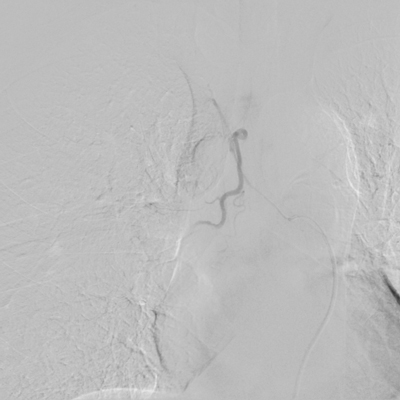

患者王某、男、55岁,因“反复间断咯血3月余”入住我院,曾因间断咯血,多次行止血药物等治疗,但症状仍有反复。此次咯血量大,病情危重,药物治疗效果差,经院内多学科讨论,在湖北民族大学附属民大医院副主任医师万金城、主治医师姚蓬指导下,制定血管介入治疗方案,并顺利完成了支气管动脉造影术+支气管动脉栓塞术,术后患者咯血症状明显好转。

术前 术后